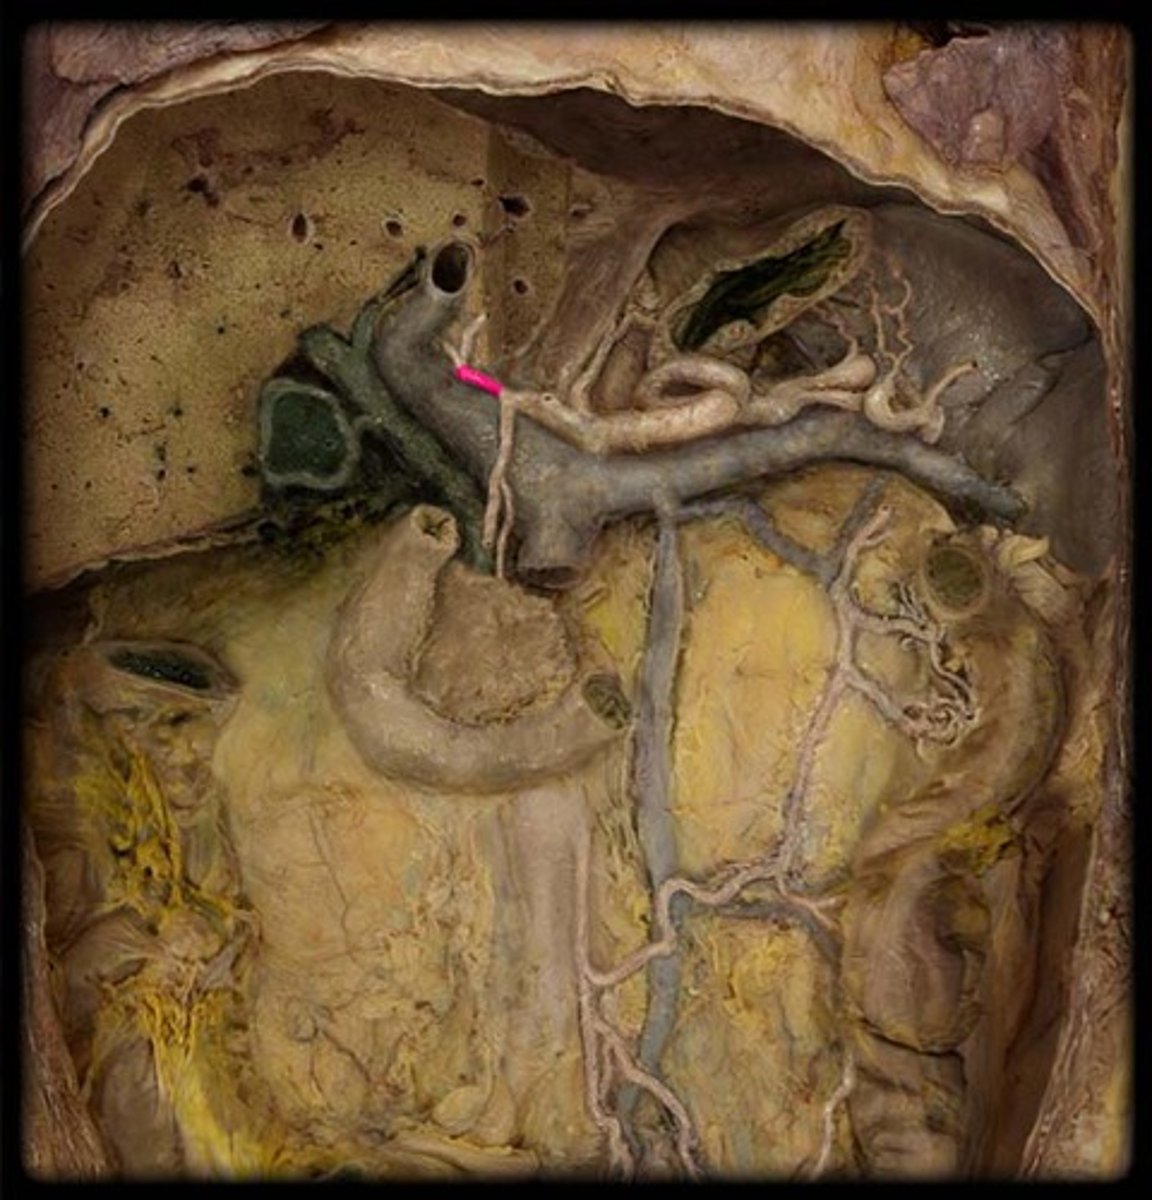

What is this?

(Proper) Hepatic artery

(Hepatic) Portal vein

(Common) Bile Duct

Porta hepatis structure consists of...

Proper hepatic artery

Hepatic portal vein

Common bile duct

Common hepatic duct

Cystic duct